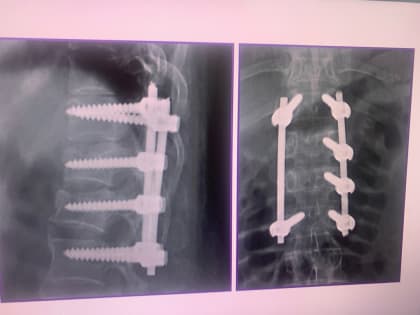

Первая операция по фиксации позвоночника у ребёнка в нейрохирургии

Врачи применили малоинвазивную методику для восстановления здоровья пациента.